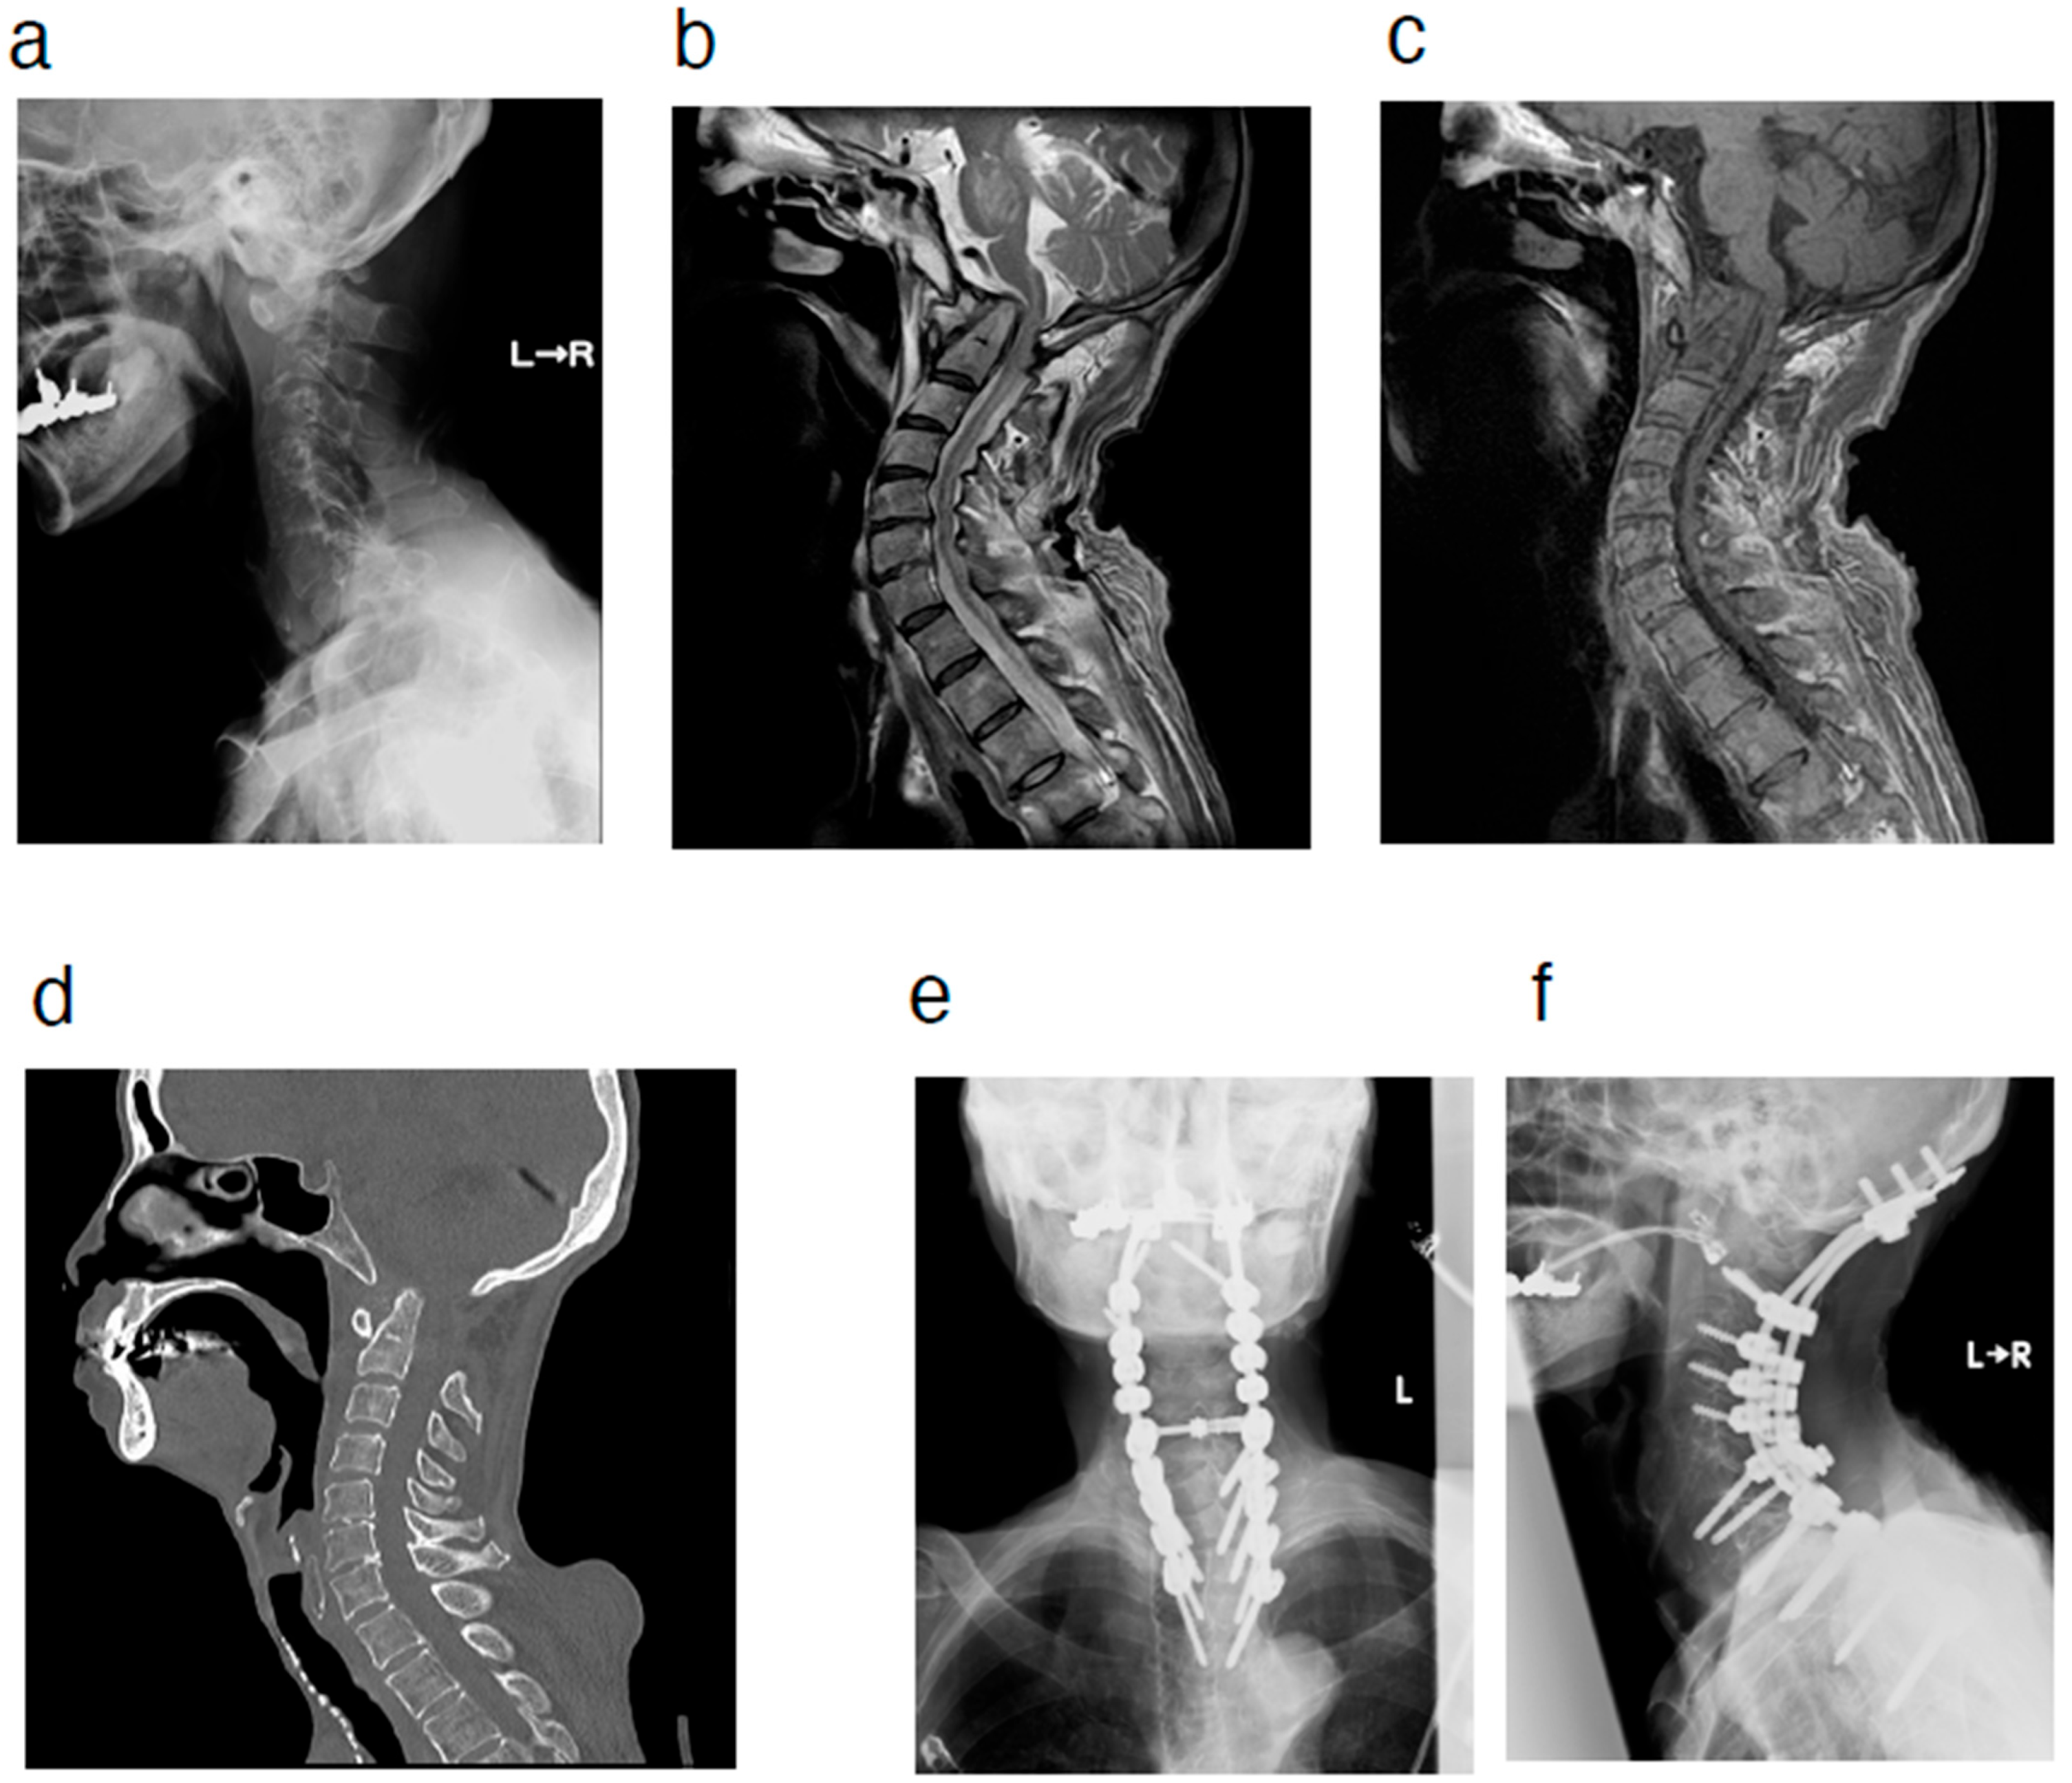

2. Case Presentation